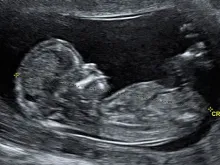

Mãe pede permissão para sepultar o seu bebê que instituição médica considera "resíduo biológico"

Em meados de 2012, Esteffany Quintana, de 28 anos, perdeu uma das gêmeas que levava no ventre, e quando se... Leia mais